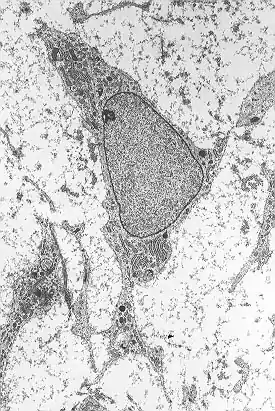

Las células madre de la mesénquima se caracterizan morfológicamente por ser células pequeñas, largas y estrechas con pocos procesos celulares. En el interior se encuentra un núcleo grande y redondo con un nucléolo prominente, rodeado de finas partículas de cromatina que delimitan y diferencian el núcleo claramente. El cuerpo celular contiene además compartimentos celulares como el aparato de Golgi, retículo endoplasmático rugoso, mitocondrias y polirribosomas. Estas células se encuentran bastante dispersas y la matriz extracelular adyacente está formada por algunas fibrillas reticulares, careciendo, sin embargo, de otro tipo de fibrillas de colágeno.[8][9]